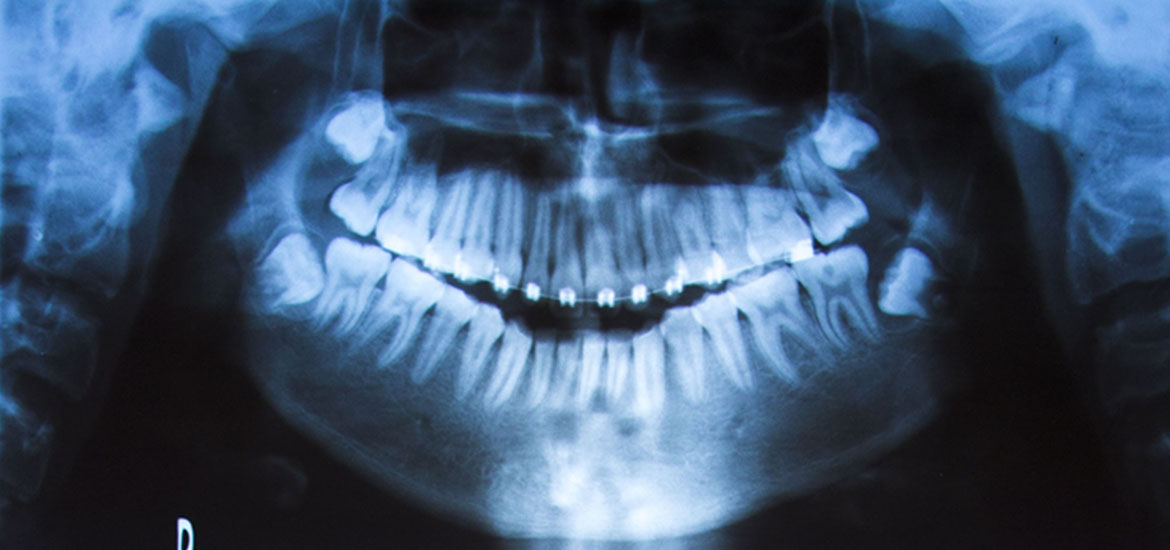

Cuando la caries en su evolución produce cavitación y ésta logra llegar a la pulpa dental, produce su inflamación y por consiguiente, dolor.

Si la pieza no es tratada, existe muerte del tejido pulpar, y si aún así no es tratada puede producir procesos infecciosos. En todos estos casos, y siempre que la estructura de la pieza dentaria lo permita, se realiza el tratamiento endodóntico, que consiste en la eliminación del paquete vasculo-nervioso, la limpieza y eliminación de bacterias dentro del conducto. También se realiza tratamientos de conductos con fines protéticos.